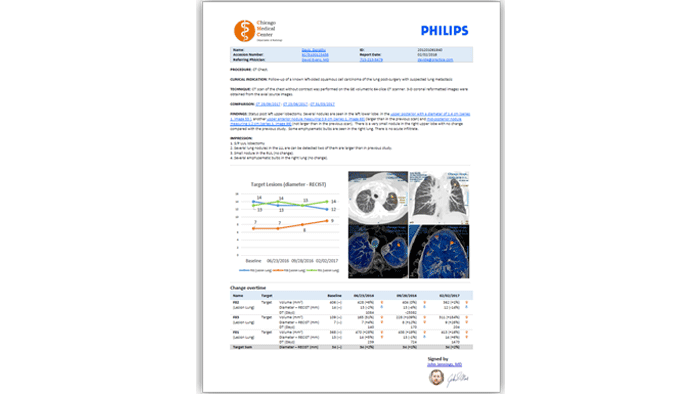

Funciones y ventajas

Flujo de trabajo de medición de oncología

Proporcionar información clínica a los especialistas es crucial, sobre todo en campos como la oncología. La aplicación Lesion Management Tool permite ofrecer seguimiento en exámenes de alto valor que requieren una planificación del tratamiento compleja, como es el caso de los exámenes oncológicos. Lesion Management Tool proporciona a los oncólogos los datos necesarios: análisis de tendencias, mediciones y marcado anatómico, entre otros.

Creación interactiva de informes multimedia

Reduzca el tiempo de respuesta de días a horas. Reconocimiento de voz, integración de RIS y PACS, inicio de sesión único e informes estructurados definidos por el usuario con datos de paciente integrados para eliminar la complejidad y la introducción manual durante la elaboración de informes de diagnóstico.

Rápida

Acelera el tiempo de respuesta con plantillas definidas por el usuario, informes estructurados y reconocimiento de voz integrado.

Integrada

Ofrece lectura y generación de informes en un solo espacio de trabajo, con imágenes clave presentadas junto con los datos y la información analítica del paciente.

Simple

Reduce los costes y mejora los resultados con un sistema fácil de implementar y de aprender a utilizar en entornos multicentro y de terceros.

Funciones y ventajas

Reducción de costes y mejora de la comunicación

Reduce la necesidad de utilizar CD y DVD. Acceso seguro y gestión de los propios datos con servicios innovadores y con valor añadido para el paciente. Eliminación de los costes de sistemas de dictado de terceros para que el tiempo de respuesta sea más rápido, lo que permite ofrecer un servicio mejor a los médicos y especialistas mediante un único sistema para una administración y una formación más sencillas.

Velocidad del reconocimiento de voz integrado

El módulo de creación interactiva de informes multimedia, con reconocimiento de voz integrado, ayuda a reducir el tiempo de respuesta. Elimina por completo la necesidad de escribir e introducir el contexto clínico o los datos del paciente. Los datos de los exámenes pueden introducirse directamente en los informes. Esto permite a los radiólogos revisar y aprobar rápidamente informes finales, a la vez que se incluye contexto clínico para los médicos especialistas.

Un espacio único de interpretación y generación de informes

Generación de informes desde cualquier lugar en el que se puedan visualizar imágenes con menor esfuerzo y menos errores. Los informes nativos sencillos y estructurados permiten una evaluación más rápida y una generación de informes de calidad a través del acceso a estudios previos con hipervínculos.

Contenido clínico fiable con navegación inteligente

Informes multimedia, que incluyen imágenes y tablas clave para una navegación más intuitiva a través de hipervínculos, lo que permite una valiosa comunicación con los pacientes. Sin necesidad de controladores especiales ni software de terceros, con menor integración y actualizaciones más simples.